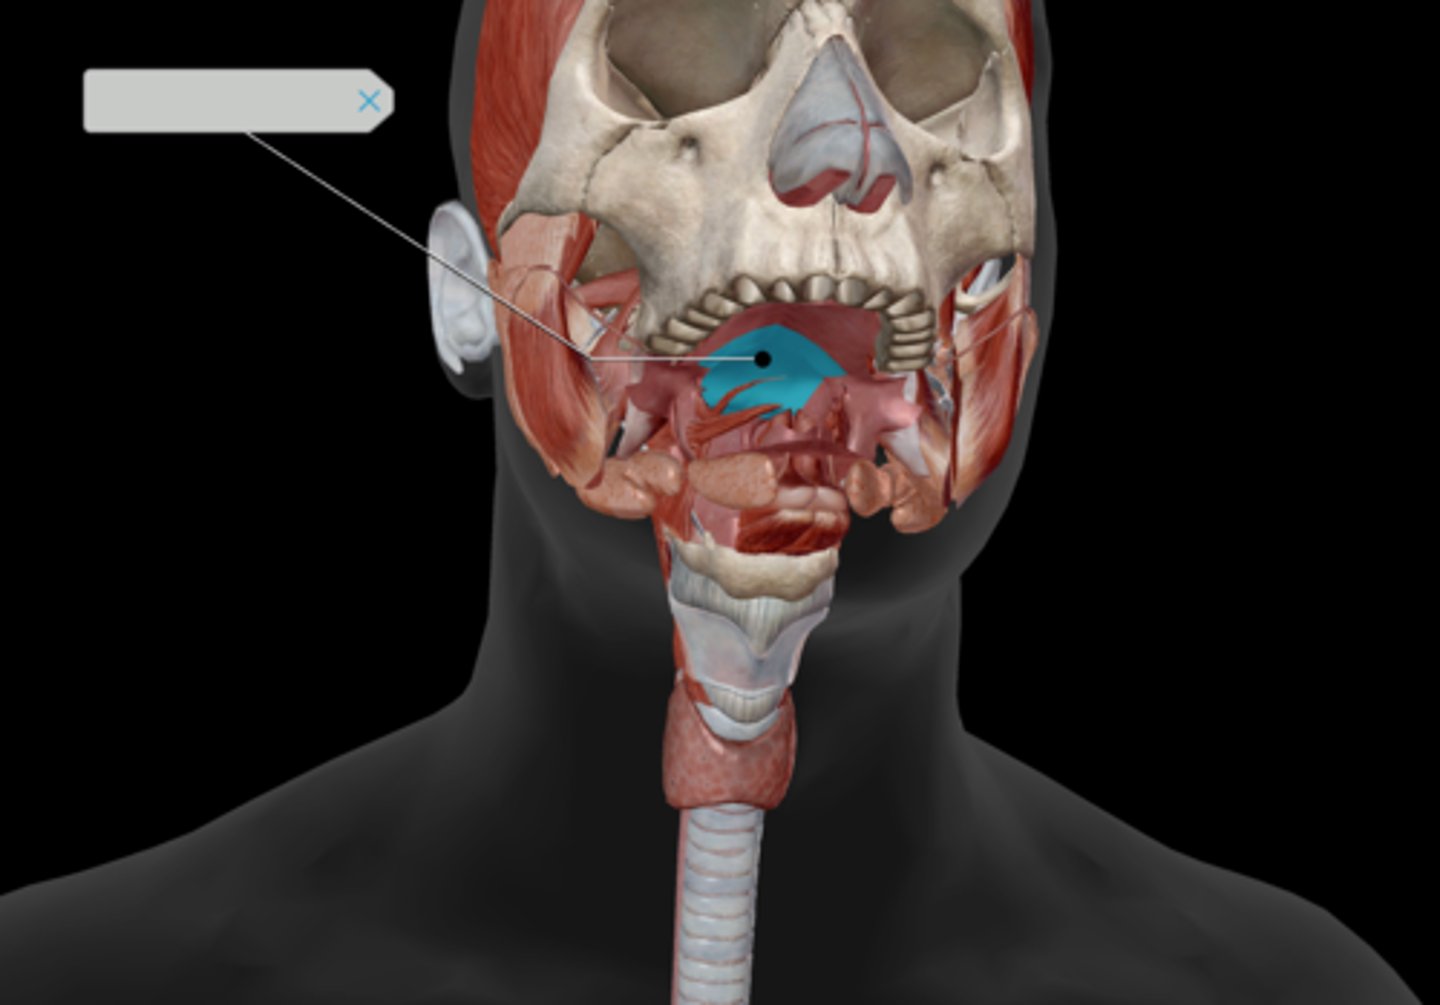

Oropharynx

Tongue

Hard palate

Soft palate

Palatine tonsil

Uvula

Parotid gland

Submandibular duct

Sublingual gland

Superficial masseter

Deep masseter

Temporalis